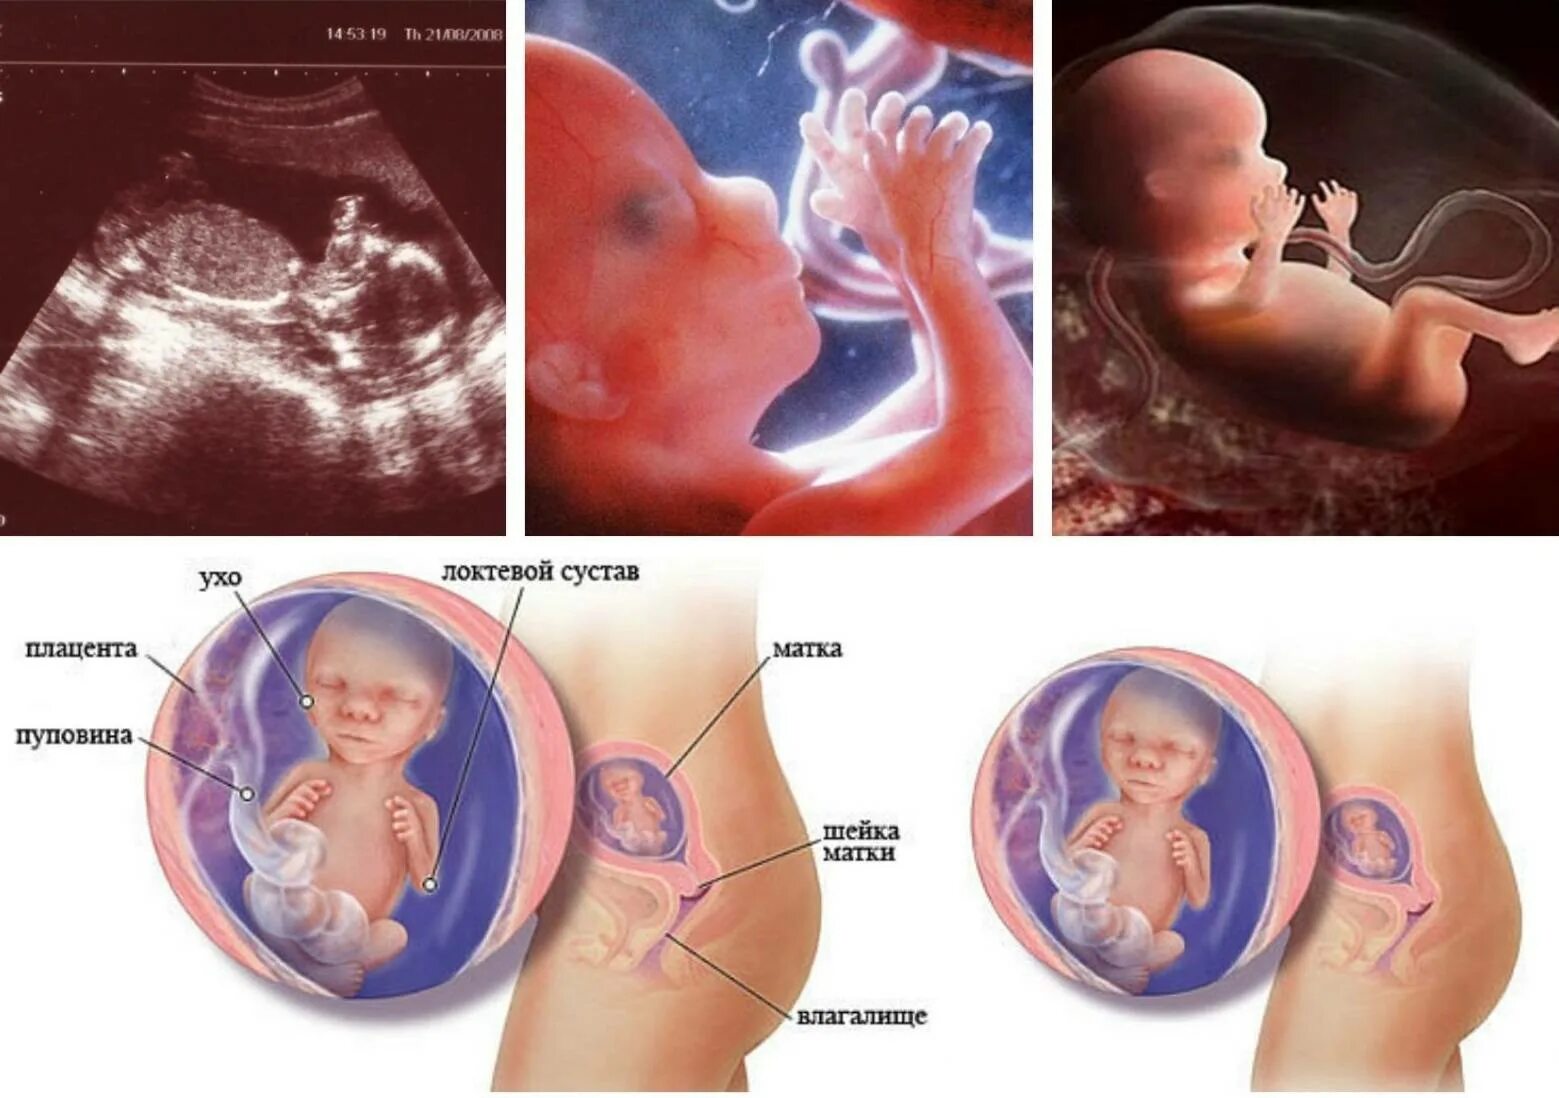

На какой неделе беременности можно почувствовать шевеление